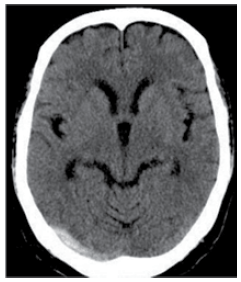

Adolescente do sexo feminino, de 14 anos de idade, é trazida ao pronto-socorro por dor de cabeça. Relata cefaleia persistente há 3 dias, a qual teve início súbito, com piora ao decúbito. Ao exame, apresenta papiledema e restrição na abdução do olho direito. Estudo de imagem demonstra a alteração a seguir.

O diagnóstico mais provável é